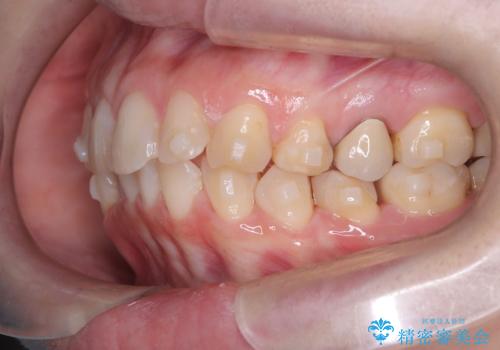

- 下の前歯のデコボコ(叢生)を気にされてご来院されました。精密な検査の結果、下の前歯を並べるスペースが不足していることが判明。患者様のご希望から、透明で目立ちにくい**インビザライン(マウスピース矯正)による治療計画を立案しました。主に歯の側面をわずかに削るIPR(歯間乳頭保護下ストリッピング)**などでスペースを確保し、下の前歯の叢生を解消することを目指します。

今回の矯正治療では、透明なマウスピース型の装置インビザラインを使用しました。目立たず、取り外しが可能なため、日常生活にほとんど影響なく治療を進めることができました。治療は、緻密に計算された計画に基づき、IPRなどで必要なスペースを確保しながら、下の前歯をスムーズに移動。これにより、長年の悩みであった下の前歯のデコボコが解消され、清掃しやすい、整った歯並びを獲得していただけました。